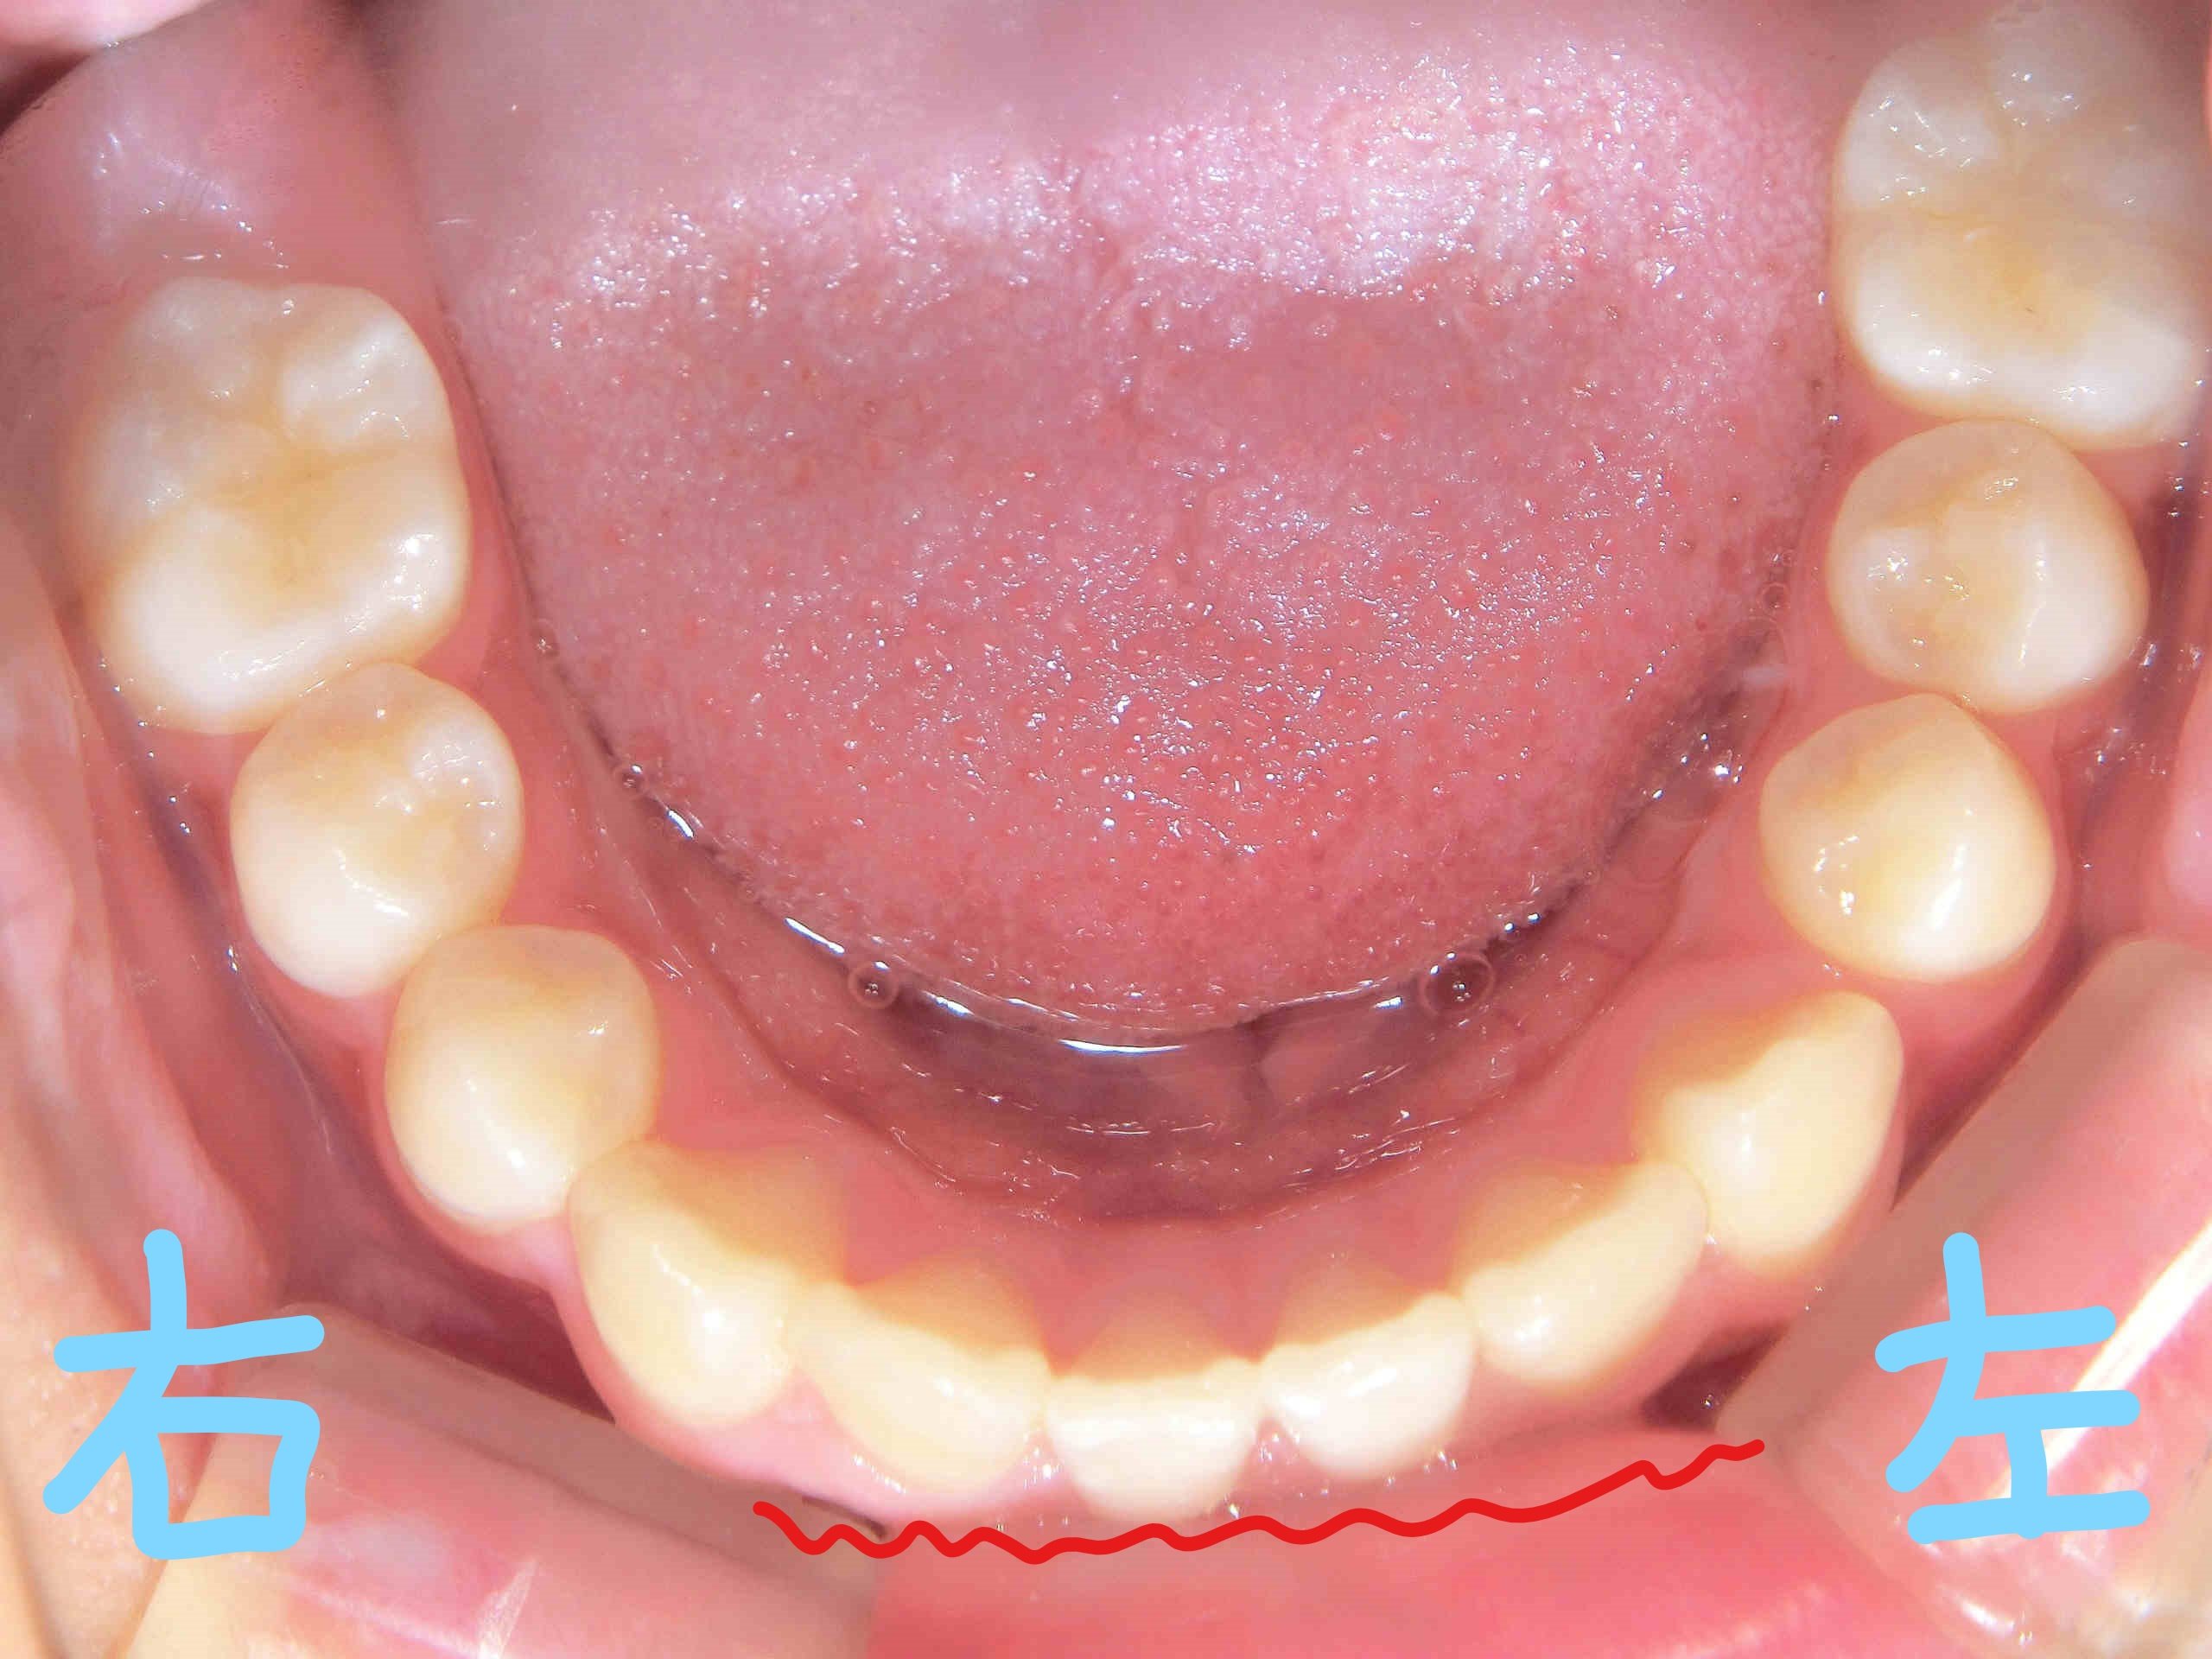

左上の写真は上顎を下から見た写真、右上は下顎を上から見た写真です。第二大臼歯が完全に萌出するまでは経過観察が必要ですが、上下顎ともに歯列の整列が進んでいる様子が確認されます。